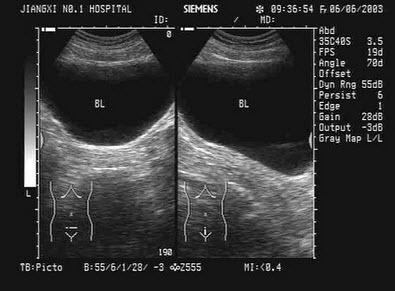

2、单项选择题

下图为宫内孕囊声像图,可见心管搏动,该胎儿至少大于多少周()

A.6周

B.9周

C.10周

D.12周

E.8周